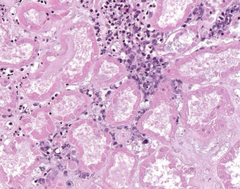

Hepatic Amyloidosis

Front

Back